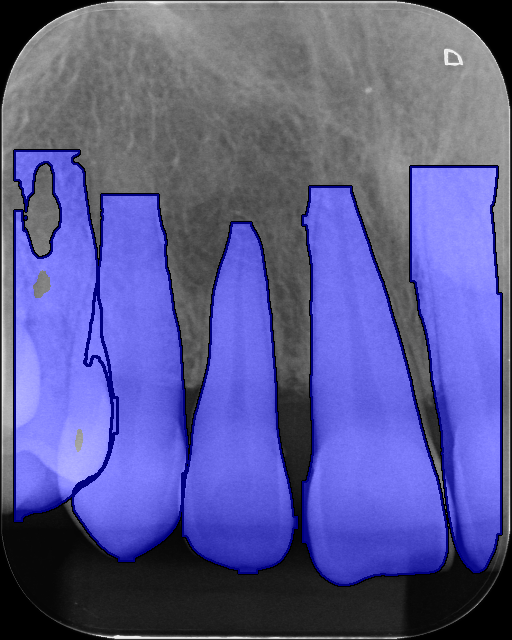

As a single trained segmentation model is to be used on our differing domain periapical dataset, which does not contain its own tooth segmentation labels, we primarily evaluated the performance qualitatively on our dataset and the cropped panoramic validation set. Additional training details and quantitative results on the auxiliary segmentation validation set are in A

During inference with the post-processing module, we intentionally tuned prediction stage hyperparameters to over-predict segmentation masks. We did this by setting the Intersection over Union (IoU) threshold to 0.70.7 and confidence threshold to 0.150.15, which predicts a large number of overlapping masks of varying quality and completeness. We then use Non-Maximum Merging (NMM) [44] with an IoU threshold of 0.10.1. This is done to combine the large number of poor quality predicted masks, that is produced by the model when qualitatively evaluated on our different domain distribution dataset, into a cohesive and higher quality tooth masks, as seen in Figure 3.

Refer to caption

(a) Before NMM

(b) After NMM

Figure 3: Images containing predicted segmentation mask overlays, for Image 1, where (a) is before NMM and (b) is after NMM.

When segmenting the teeth in the image, we expect occasional false positive predictions from the instance segmentation model. This in turn, produces multiple redundant segmentation mask orientation angles, which are filtered out during post processing.